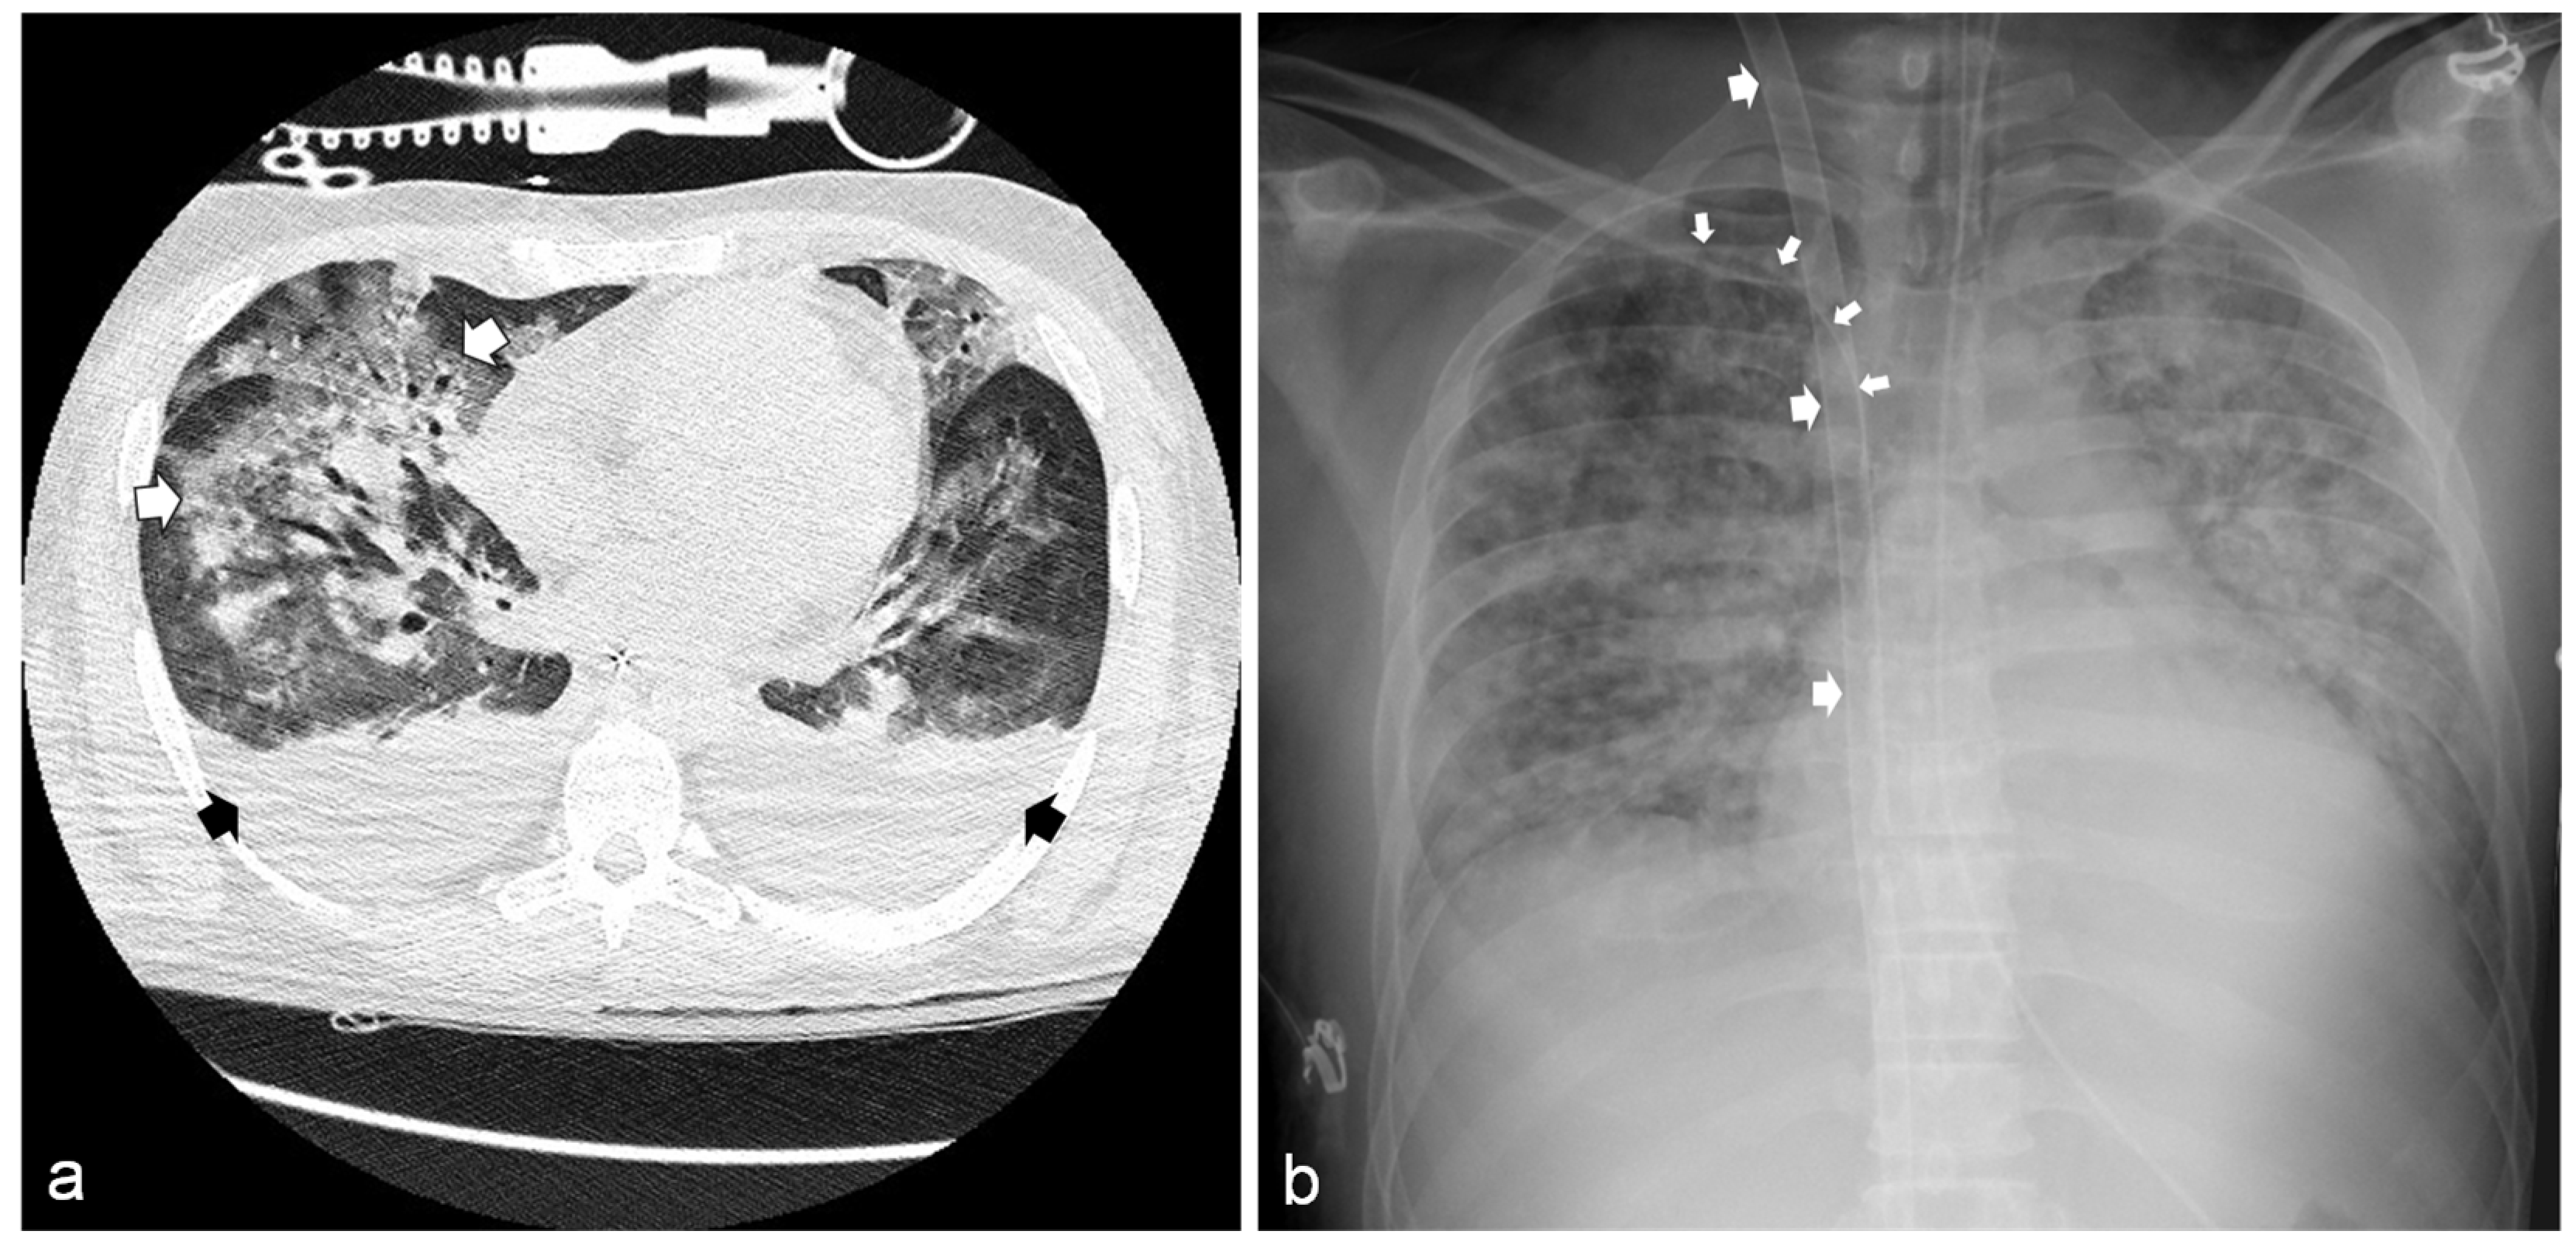

2.2. 12 h from ED Admission: Transfer to the General Intensive Care Unit